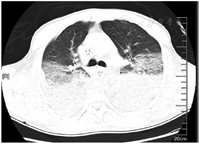

患者入院后立即予面罩吸氧、置胃管,甘露醇125 ml联合25%硫酸镁20 ml(每8小时1次)导泻;入院后12 h内予纯牛奶2 000 ml胃管内分次注入后,重复负压抽吸胃液;分别于7月6日0:15、12:50行血液灌流2 h,同时予甲强龙60 mg(每12小时1次)静脉滴注减轻肺水肿和渗出以及抗感染(哌拉西林钠/他唑巴坦4.5 g,每8小时1次),异甘草酸镁0.2 g静脉滴注1次/d保肝,泮托拉唑40 mg静脉滴注1次/d抑酸等对症支持治疗。入院当天患者发热,体温37.9 ℃、血氧饱和度下降至85%,予经口气管插管、呼吸机辅助呼吸、镇痛镇静治疗,患者气道内吸出黄白黏液样痰,复测P/F 255 mmHg[呼气末正压(PEEP)5 cmH2O]。入院后第2天予鼻饲肠内营养混悬液(SP)20 ml/h。入院后第4天肠内营养加量至50 ml/h,P/F下降至149 mmHg(PEEP 8 cmH2O);行气管镜检查示气道充血、水肿,部分气道黏膜坏死、剥脱;肺泡灌洗液培养示铜绿假单胞菌,予限制性液体管理。入院后第5天行经皮气管切开术,逐步撤离镇痛镇静药物,患者口唇破溃伴糜烂,予苏打水清洁口腔;行胸部CT检查示两肺多发渗出,考虑吸入性肺炎、双侧胸腔积液、腹腔积液(图1)。入院后第6天甲强龙减量为60 mg 1次/d,并加用低分子肝素4 000 IU预防深静脉血栓形成和肺微小血栓形成。入院后第10天停用甲强龙,后继续抗感染、全肠内营养支持、气管镜吸痰、肺保护性通气、肺复张及对症支持治疗。入院后第11天患者P/F上升至210 mmHg,胸部CT示两肺渗出较前明显吸收(图2)。

两肺多发渗出、双侧胸腔积液